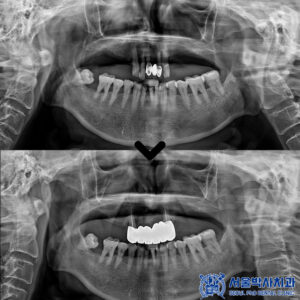

위 환자분은 위 앞니가 심하게 흔들리면서

씹을 때마다 불편감을 느낀다고 하셨는데요.

진단 결과, 문제의 치아는 위 앞니 중에서도

정중앙에 위치한 오른쪽 큰 앞니로,

치아 상태도 많이 나빠져 있었고

만성 치주염으로 인해 치근 끝에

염증이 크게 퍼져 흔들림이 있는 상태였습니다.

치료 마무리 후 사진입니다.

치료 후 환자분께서 거울을 보시면서

이렇게 자연스럽게 치료될 줄 몰랐다고 하시며,

임플란트 해야 하는 줄 알았는데 자연치아를

살릴 수 있어서 너무 만족한다고 좋아하셨습니다.